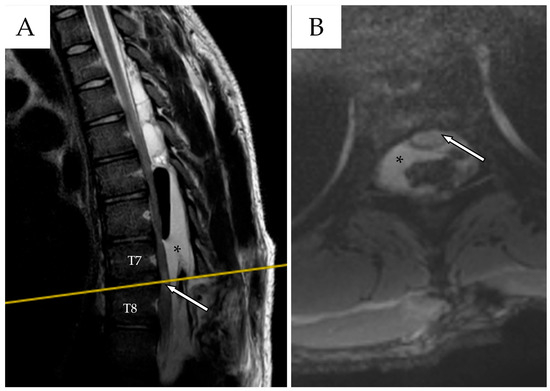

Whole-spine contrast-enhanced Magnetic Resonance Imaging (ceMRI) demonstrated a posterior, extradural intraspinal lesion extending from T2 to T8, causing significant compression of the dural sac and spinal cord (Figure 1). The lesion was formed by two components: a cranial one (T2–T4) and a larger caudal one (T5–T8). The area of maximal spinal cord compression was identified at T7–T8, where subtle intramedullary T2 hyperintensity was observed, suggestive of early spinal cord changes consistent with possible myelopathy (Figure 2). The lesion appeared hyperintense on T2-weighted images, isointense with CSF, and showed no contrast enhancement—findings consistent with a spinal arachnoid cyst.

Figure 1. (A) Cervical spine ceMRI, sagittal section, TSE T2-WI. The cranial portion of the SAC is visible at the T2 level. To facilitate counting, the cervical vertebrae and the first two thoracic vertebrae are marked with their corresponding names. (B) Thoracic spine ceMRI, sagittal section, TSE T2-WI. The SAC is visible in its entirety, composed of a smaller cranial portion (T2–T4, white asterisk) and a larger caudal portion (T5–T8, black asterisk). The dural sac is easily identifiable (white arrows with black outlines), confirming the extradural location.